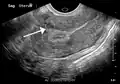

A very large (9 cm) fibroid of the uterus which is causing pelvic congestion syndrome as seen on ultrasound -

A small uterine fibroid seen within the wall of the myometrium on a cross-sectional ultrasound view -